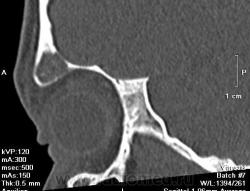

Девочка, 13 лет. К сожалению анамнеза толком не знаю, девочку не видела, снимали без меня. Основная жалоба на наличие "шишки". В направлении - исключить объемный процесс. Написала, что вероятнее всего фиброзная дисплазия. При несоответсвии клиническим данным рекомендуется биопсия. А сомнения остались. Как вы считаете что это может быть?

Вряд ли это псевдотумор. Мягкие ткани орбиты не изменены. Все в пределах кости. Кость вздута. Гемангиома - это вариант, на мой взгляд.

Шишка по верхнему краю орбиты.

Но, тут, ведь два патологических процесса - один в лобной пазухе, другой - в орбите?

Это "объём" в орбите?

Это нижний полюс "образования". Шишка похоже не связана с пазухой, а в орбиту вдается за счет вздутия кости. Завтра постараюсь выложить еще коронарных срезов.

Коронарные срезы.

Да я на первое место поставила фиброзную дисплазию. И порекомендовала биопсию при несоответствии клиническим данным. Надеюсь не ошиблась.

Жалко, что Вы девочку не видели, есть синдром Олбрайта, изменения идут не только костные, но и идет преждевременное половое созревание, так же наличие пегментных пятен. Возможно фиброзная дисплазия орбиты, только не приближена к классике.

Фиброзная дисплазия с обструкцией дренажа фронтального синуса. Интересное наблюдение. По синдрому Олбрайта - согласен с коллегой v1tal, ещё характерен невысокий рост (гипостатура).

Мой грех, девочку упустила. Спасибо, Марио, за ссылки. Правда очень похоже на фиброзную дисплазию.

Типичное место локализации метастаза нейробластомы у детей. Нужно обследовать брюшную полость и забрюшинное пространство